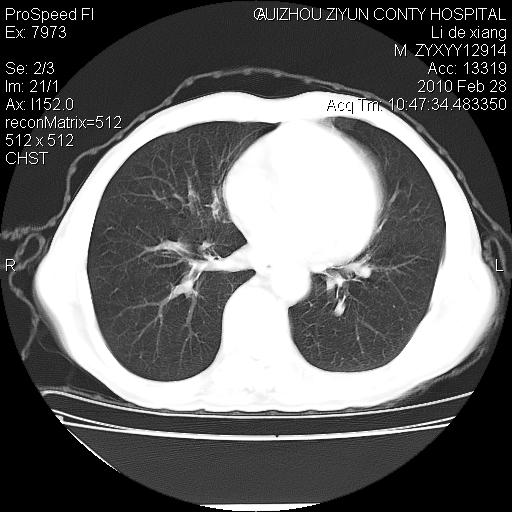

标题: CT24776:男 71Y 咳嗽咳痰胸痛两月,伴声音嘶哑。 [打印本页]

标题: CT24776:男 71Y 咳嗽咳痰胸痛两月,伴声音嘶哑。

左侧中央型肺癌伴左肺上叶阻塞性肺炎及节段性不张可能性大,建议纤支镜检查!

左侧中央型肺癌伴左肺上叶阻塞性肺炎及节段性不张可能性大,建议纤支镜检查!纵隔淋巴结转移.

左侧中央型肺癌伴左肺上叶阻塞性肺炎及纵隔淋巴结转移。

左肺门部肿块,伴左上肺斑块影,周边模糊,支持左肺中央型肺癌伴节段性不张及阻塞性肺炎,结合支气管镜检查。

左上叶支气管狭窄,阻塞性病变,肺门肿块,纵隔及肺门淋巴结增大,中央性肺癌